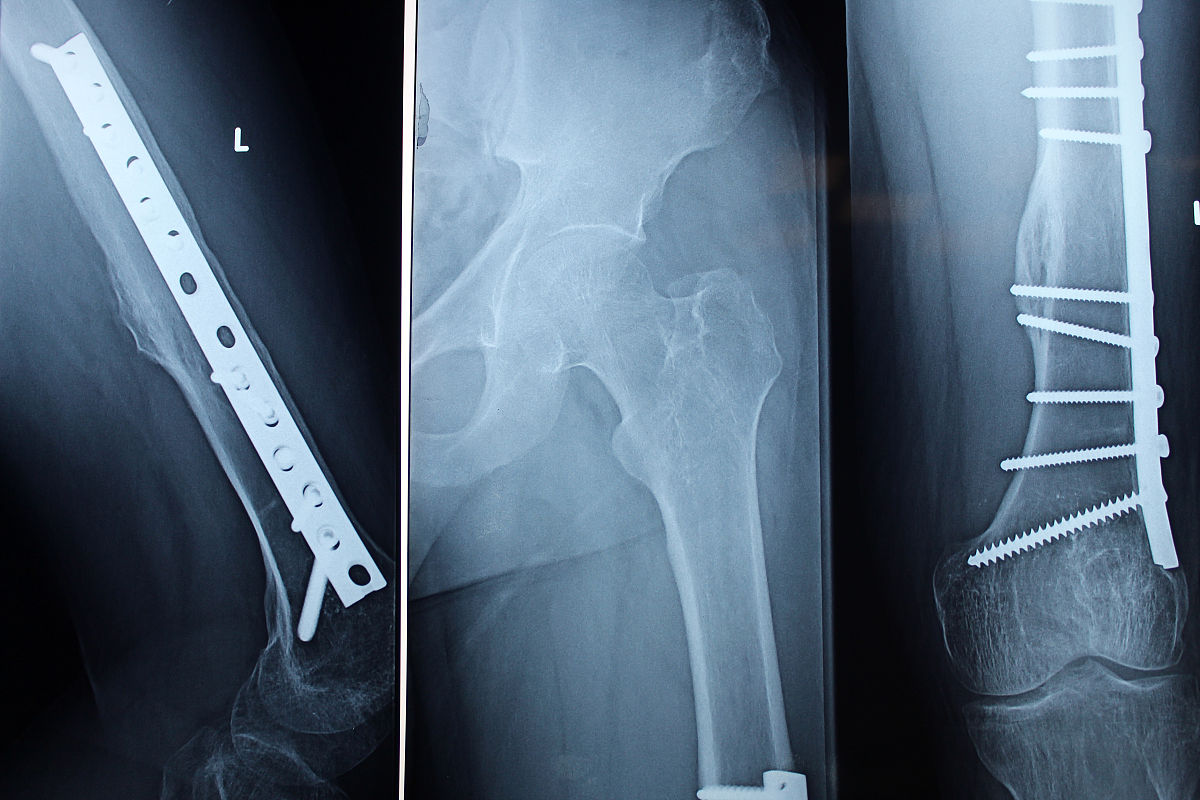

左股骨粗隆间骨折是一种常见的骨折类型,治疗方法多样。闭合复位PFNA内固定术是一种常用的治疗方法,其重要性主要体现在以下几个方面:

1. 促进骨折愈合:通过闭合复位PFNA内固定术,可以将骨折段复位并固定,稳定骨折端,促进骨折的愈合。内固定器材的使用可以提供足够的稳定性,减少骨折断端的移位,有利于骨折愈合。

3. 早期功能恢复:闭合复位PFNA内固定术可以提供稳定的内固定,使患者在早期就能够进行关节活动和负重,促进肌肉力量的恢复和关节功能的恢复。相比传统的外固定或开放手术,闭合复位PFNA内固定术的恢复时间更短,患者能够更早地恢复正常生活和工作。

4. 减少并发症:闭合复位PFNA内固定术是一种微创手术,创伤小,术后并发症较少。相比开放手术,闭合复位PFNA内固定术的感染率、创伤愈合不良率等并发症发生率较低。

综上所述,闭合复位PFNA内固定术对于左股骨粗隆间骨折的治疗具有重要的意义,可以促进骨折愈合,保护神经血管,促进早期功能恢复,减少并发症的发生。

左股骨粗隆间骨折闭合复位PFNA内固定术治疗:优势与重要性